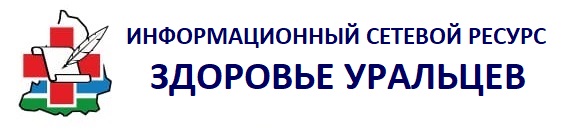

Врачи Свердловского госпиталя для ветеранов войн успешно провели операцию по восстановлению черепа капитана, который едва не погиб в зоне специальной военной операции при артиллерийском обстреле. Минно-взрывное ранение головы у офицера сопровождалось разрушением более 90% лобной, височной и теменной костей черепа, лобных пазух и костей носа. Бойцу удалось сохранить жизнь благодаря оперативной эвакуации, этапному лечению и высокотехнологичной медицинской помощи, доступной в учреждениях здравоохранения в рамках реализации национального проекта «Продолжительная и активная жизнь».

Пациента, получившего тяжелейшее ранение во время боевых действий, после стабилизации состояния доставили в Свердловский госпиталь для ветеранов войн. Команда специалистов провела мужчине сложнейшую реконструкцию переднего отдела черепа с применением цифровых технологий и отечественных разработок.

Специалисты провели 3D-моделирование черепа, воссоздали виртуальный прототип анатомической формы, а затем в лаборатории 3D-технологий госпиталя изготовили индивидуальную танталово-титановую пластину, точно соответствующую объёму и контуру разрушенного участка.